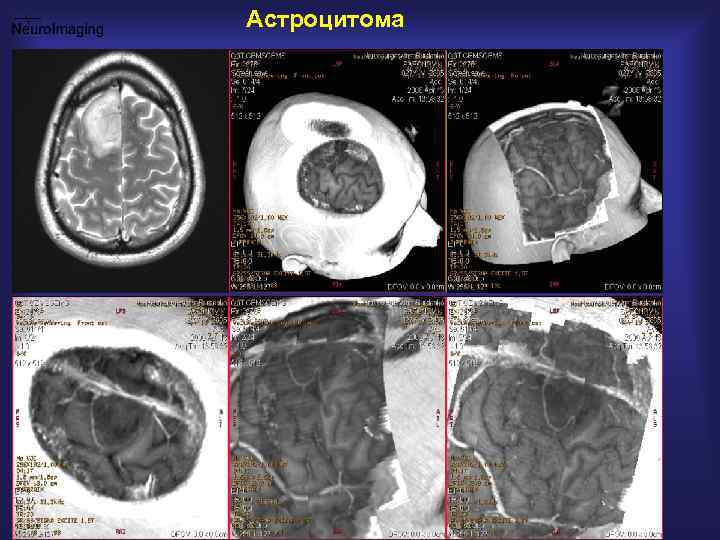

Астроцитома